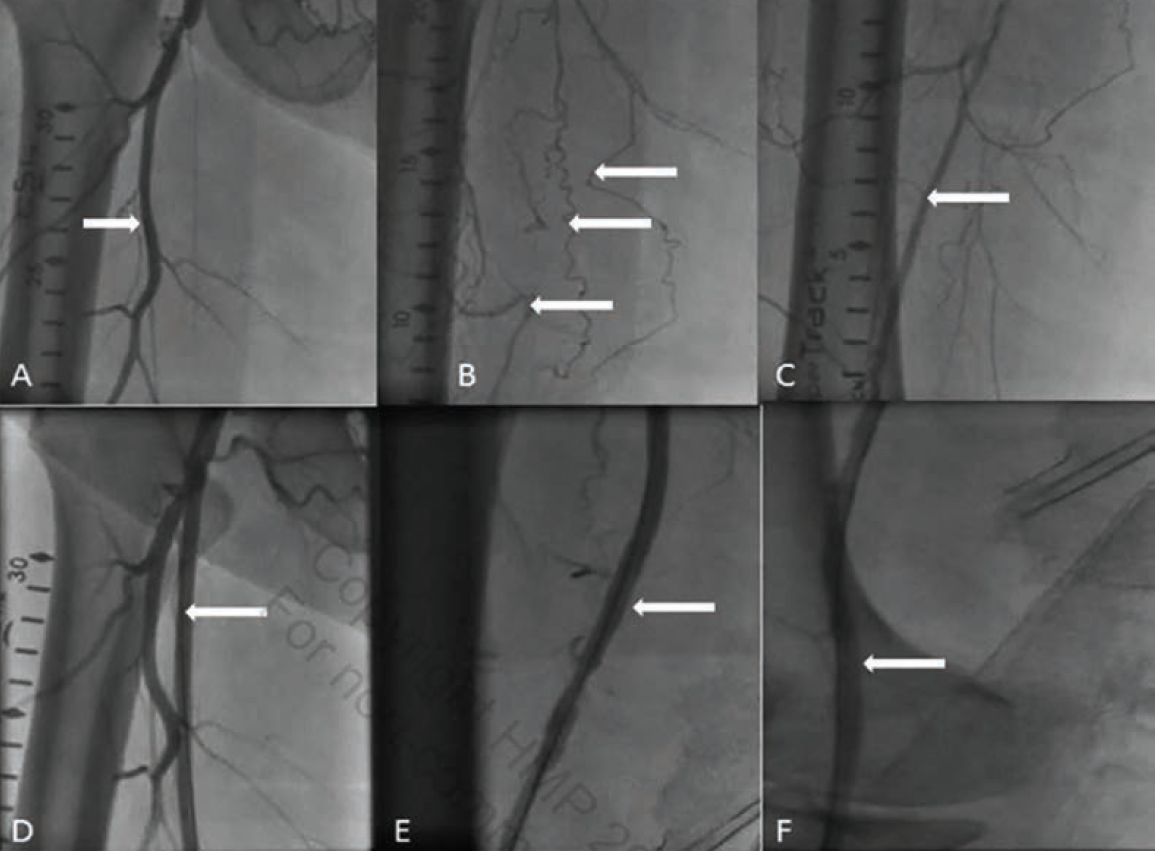

Case 2: OCT-Guided Atherectomy and Drug-Coated Balloon for SFA Lesions

A 62-year-old female with history of hypertension, hyperlipidemia, diabetes, and known PAD was referred for management of lifestyle-limiting claudication of her right lower extremity despite maximal medical therapy. Her right lower-extremity ABI was 0.7, and she was referred for invasive peripheral angiography and possible intervention. A peripheral angiogram showed focal sequential lesions in her right SFA (Figure 3A). Using right groin access, a 6 Fr crossover sheath was placed. An .014-inch guidewire was advanced into the popliteal artery and OCT imaging was performed at baseline (Figure 4A-C). Measurements were made to delineate an accurate reference vessel diameter (Figure 4B-C) as well as minimal luminal diameter (Figure 4A) at the lesion sites. A fibrocalcific plaque was well described at the lesion site (Figure 4A). We performed OCT-guided directional atherectomy of the focal lesions using a Pantheris device (Avinger) (Figure 5A-B), followed by balloon angioplasty with a 6.0 mm x 80 mm drug-coated balloon with good results (Figure 3B-E). Repeat OCT imaging showed plaque removal without any dissection, clot, or residual significant stenosis (Figures 4D and 4F). The patient was treated with dual antiplatelet therapy for 1 month with significant improvement in her symptoms during follow-up.